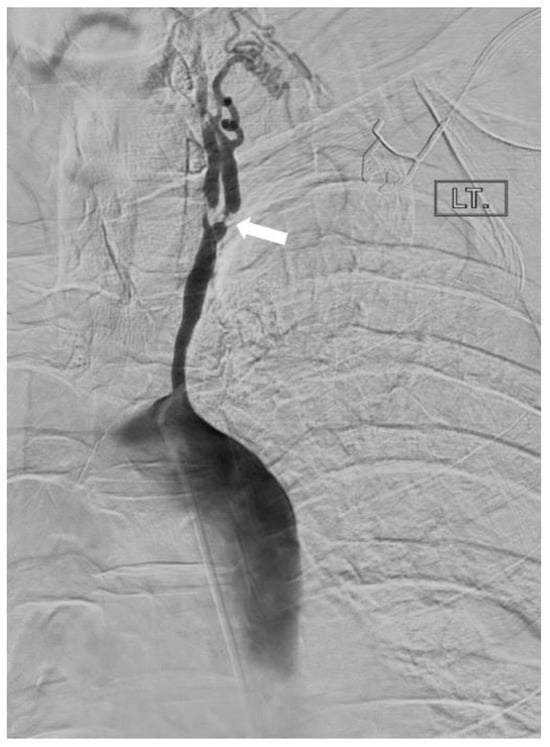

2.1.2. Takayasu’s Arteritis